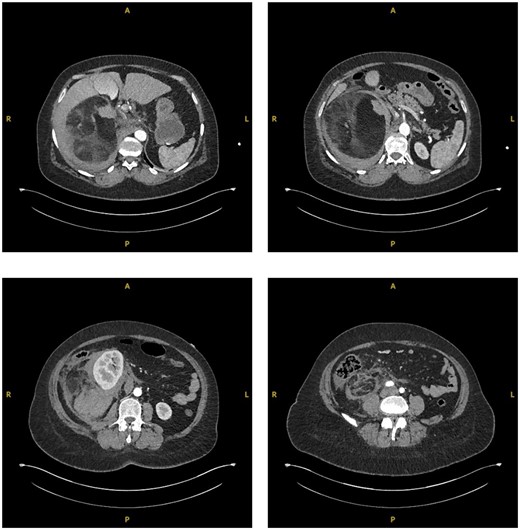

A 55-year-old Caucasian female presented to the emergency department (ED) after falling from sitting on a static pushbike onto her right flank. She immediately incurred right flank pain with nil other symptoms at time of the event. Her medical history was insignificant and she did not take any regular medications. Blood tests on admission indicated there may be an intra-abdominal injury due to raised lactate of 3 and a blood pH of 7.304. An urgent CT abdomen and pelvis (CTAP) with contrast was performed which showed a large (15.2×13.8 cm), predominantly fat containing mass in the right suprarenal region causing displacement of the right kidney and pancreas, with surrounding hyperdense fluid suggestive of acute retroperitoneal haemorrhage (Fig. 1).

Coronal (a) and transverse (b) sections of initial CT imaging with contrast showing large lesion with heterogeneous hypodense areas with surrounding haematoma (arrowed).